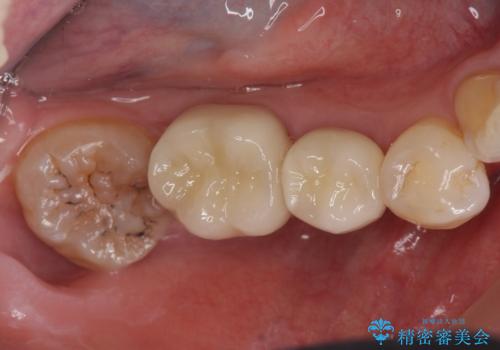

詰め物の下が虫歯 つぎはぎの歯をしっかり治療

詰め物の下が虫歯になっていました。

虫歯をしっかりとった後、セラミックで修復しました。

詰め物の下の虫歯は特に奥歯は大きかったのですが、神経を取らずに済みました。